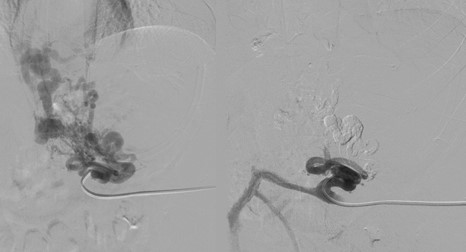

Dùng kim Angiocath chọc vào nhánh TM lách dưới hướng dẫn siêu âm, sau đó dùng dụng cụ can thiệp dưới hướng dẫn của DSA đi vào các nhánh TM cấp máu cho búi giãn bao gồm TM vị trái, TM vị sau và TM vị ngắn, chụp chọn lọc từng nhánh, bơm vật liệu tắc mạch là keo sinh học, chụp đánh giá lại sau mỗi lần chụp để có thể nút tắc triệt để.

tm nach 12

Hình 3: Kỹ thuật xuôi dòng (A) tiếp cận và chụp búi giãn qua tĩnh mạch lách; (B) nút tắc nhánh nuôi bằng keo